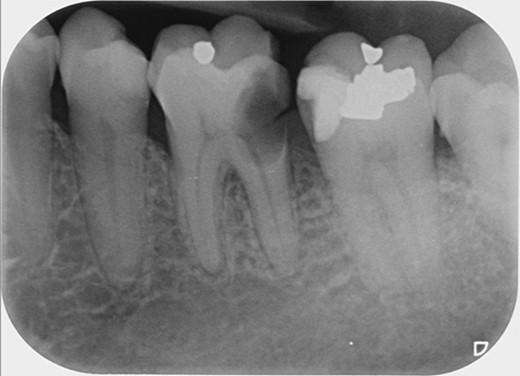

A 59-year-old male patient presented with a complaint of pain while biting on his lower left posterior teeth. Clinical examination revealed an extensive amalgam restoration on the lower left first molar (tooth 36) with a fractured restoration and secondary caries on the lingual aspect. The tooth was non-responsive to thermal testing and electrical pulp sensibility testing (EPT) and was tender to percussion. Radiographic examination showed radiolucency beneath the restoration on the mesial root surface, indicative of caries, along with furcation involvement and peri-radicular radiolucency. The tooth was diagnosed with pulpal necrosis and symptomatic apical periodontitis associated with extensive root caries (Fig. 6 and 7).

Clinical photograph of tooth 36 showing extensive amalgam restoration on mesio-occlusal-disto-bucco-lingual (MODBL).

Periapical radiograph of tooth 36 shows large radiopacity, indicating a restoration on the crown extending to the mesial root surface. Radiolucency was detected beneath restoration on the mesial root surface, indicating caries. Peri-radicular radiolucency was observed in the furcation region.